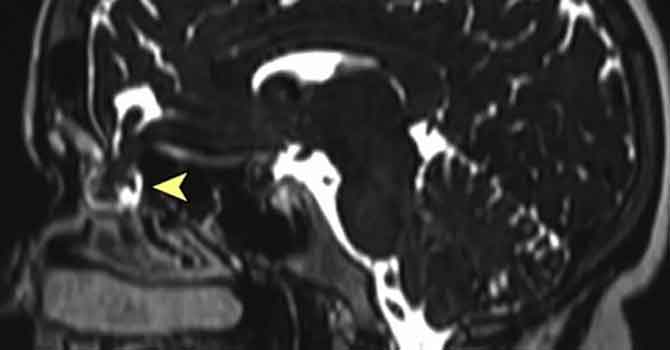

Koronavirüs testi sırasında kafatası duvarı delindi